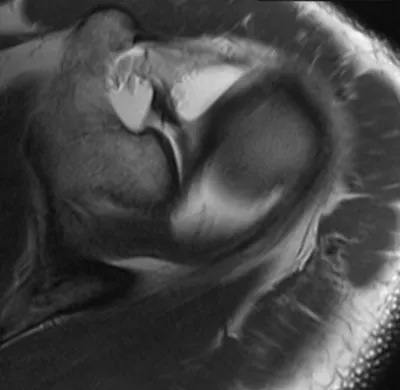

SLAP tear (Superior Labrum Anterior and Posterior)

Arthrogram

4/11/2026